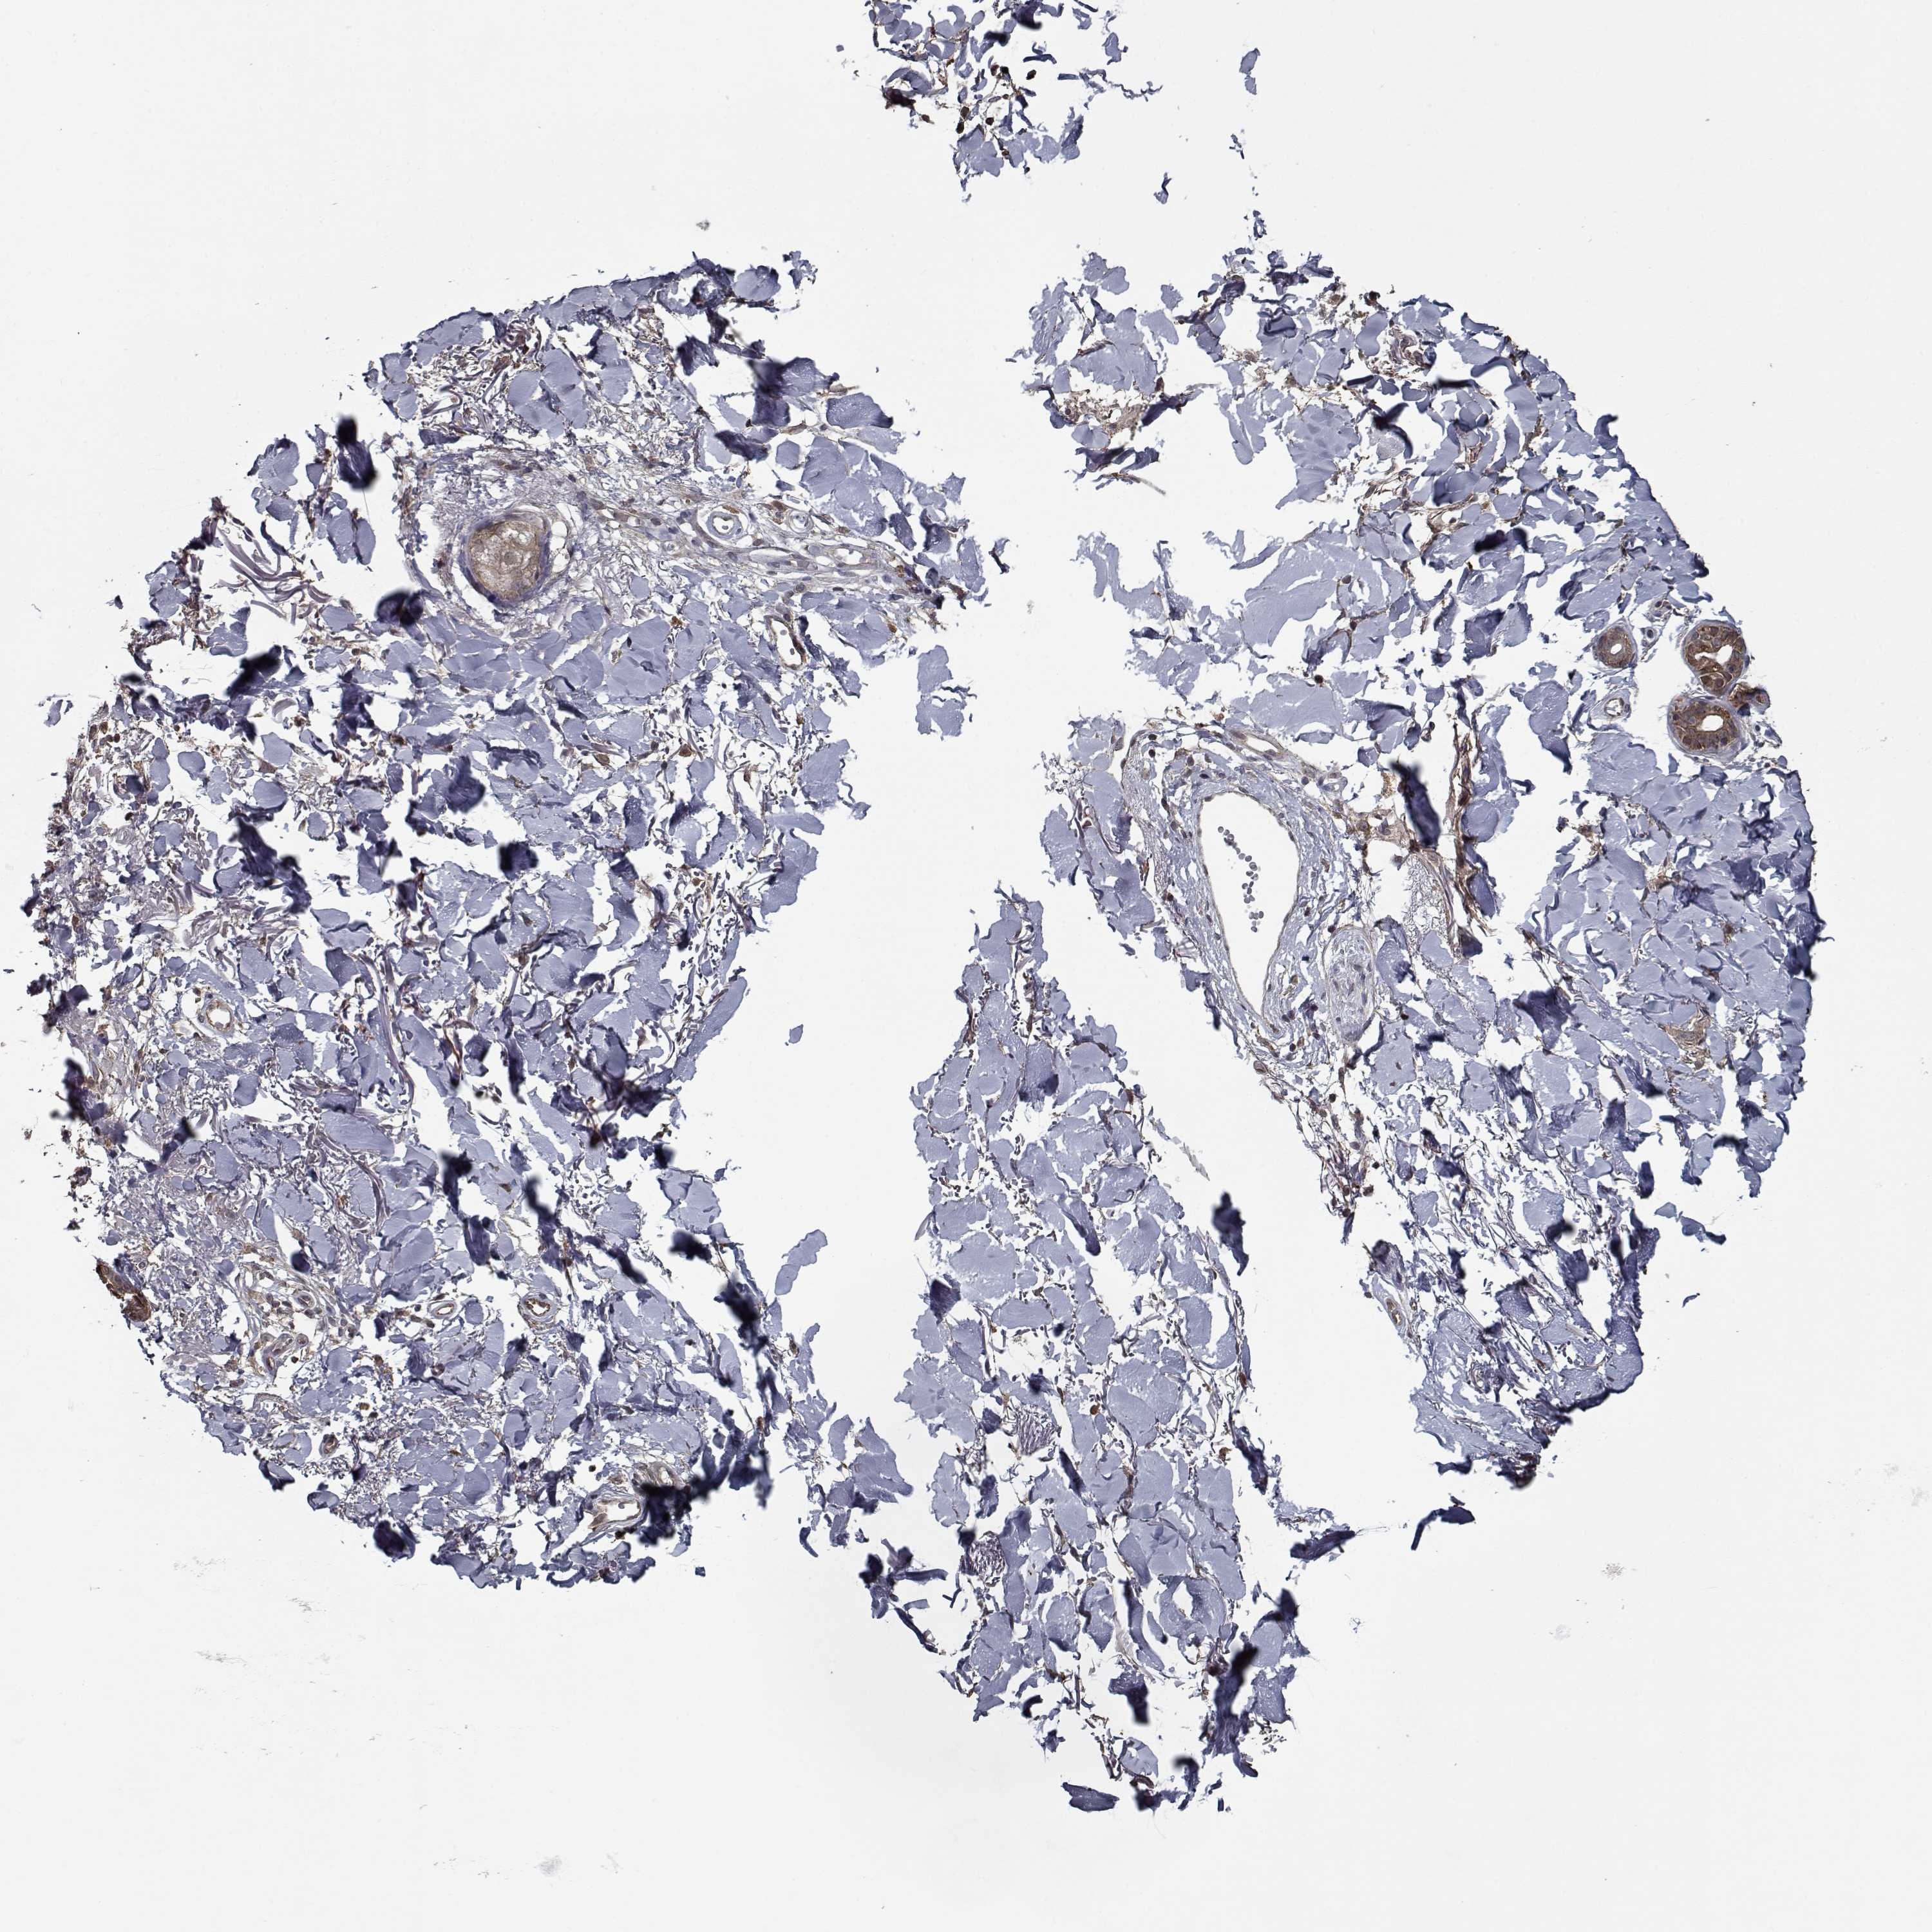

Basal cell and squamous cell cancer

SKIN CANCER - Protein expressioni

A mouse-over function shows sample information and annotation data. Click on an image to view it in a full screen mode. Samples can be filtered based on level of antibody staining by selecting one or several of the following categories: high, medium, low and not detected. The assay and annotation is described here.

Antibody stainingi

Antibody staining in the annotated cell types in the current human tissue is reported as not detected, low, medium, or high, based on conventional immunohistochemistry profiling in selected tissues. This score is based on the combination of the staining intensity and fraction of stained cells.

Each image is clickable and will lead to virtual microscopy that enables deeper exploration of all samples and also displays staining intensity scores, fraction scores and subcellular localization as well as patient and tissue information for each sample.

Antibody HPA056511

Staining

High

Medium

Low

Not detected

Intensity

Strong

Moderate

Weak

Negative

Quantity

>75%

75%-25%

<25%

None

Location

Nuclear

Cytoplasmic/membranous

Cytoplasmic/membranous,nuclear

Squamous cell carcinoma, NOS